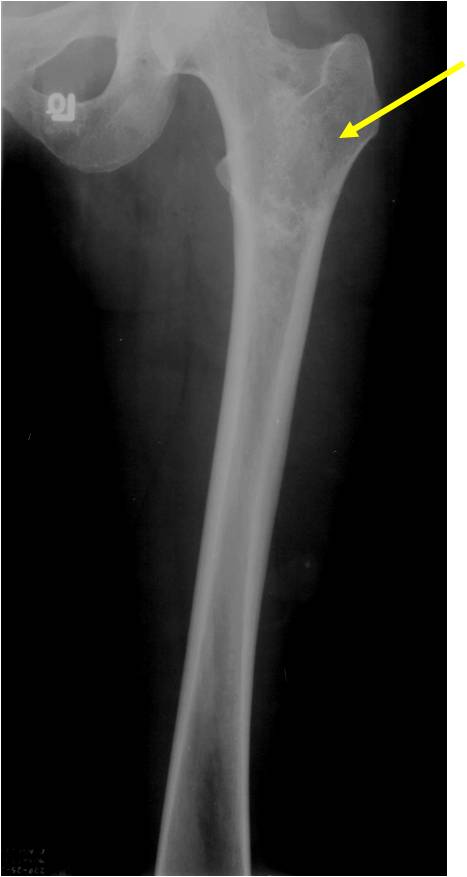

- Proximal Humerus, Femur most common long bones

- Localized, radiolucent defect usually with punctate calcifications

- Calcifications are stippled, punctate, popcorn like calcifications and “Ring and Arc” calcifications

- Most commonly found in metaphysis

- Geographic lytic lesion

- Central often metaphyseal in long bones

- Chondroid matrix with calcifications in majority of tumors

- There should never be any cortical destruction nor a soft tissue component. If this exists then the tumor must be a chondrosarcoma.

- Endosteal scalloping and cortical expansion is acceptable for phalangeal tumors. In most benign long bone cartilage tumors there is minimal endosteal scalloping but there should be no cortical expansion nor thickening. There should be no cortical destruction and no soft tissue component associated with an enchondroma. Cortical destruction, periosteal thickening, cortical expansion and a soft tissue component indicates a chondrosarcoma of the long bone.

- Cortical destruction and a soft tissue mass

- Periosteal reaction and thickening

- Endosteal erosion>2/3 cortical thickness on a CT scan

- Size greater than 5 cm